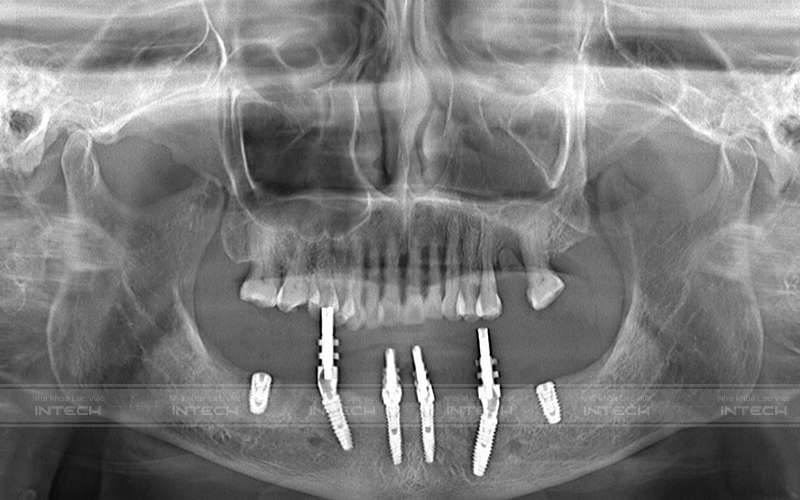

Sau khi thăm khám kết hợp chụp CT Cone Beam, Scan trong miệng, các bác sĩ đã đưa ra kế hoạch điều trị cho cô Minh:

• Cắm 4 trụ Implant hàm dưới, phục hồi 12 răng

• Khôi phục 95% chức năng ăn nhai

Hình ảnh phim chụp sau cấy ghép implant của cô Minh (Ảnh: Nha khoa Lạc Việt)